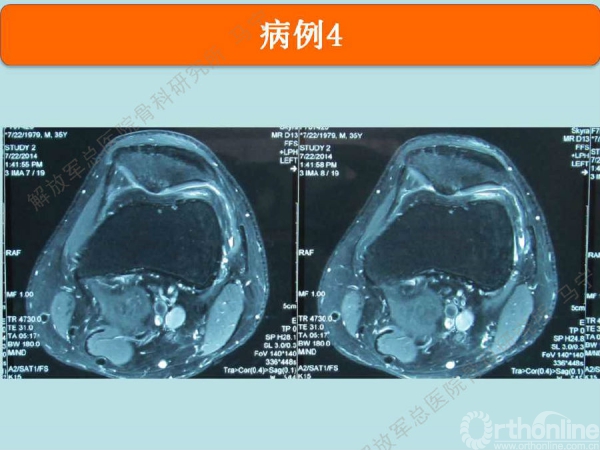

病例-4

姜**:男,33岁 ,双膝疼痛,活动受限1年,曾经打过玻璃酸钠,效果都不理想,来我院行软骨修补术,MRI显示髌骨软骨下骨增生明显,并开始磨损滑车。

术中显示软骨损伤的面积比核磁上的范围要大很多。